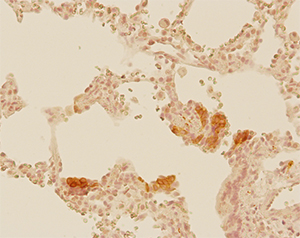

Project V: Pulmonary neuroendocrine system in SIDS

Infants who have died of sudden infant death syndrome (SIDS) show hyperplasia of pulmonary neuroendocrine cells. This project investigates the contribution of the pulmonary neuroendocrine system to the pathogenesis of SIDS. Since pulmonary neuroendocrine cells are innervated, we focus on neural regulation of pulmonary neuroendocrine secretion and the role of bioactive neuropeptides and amines secreted from pulmonary neuroendocrine cells in lung pathophysiology.